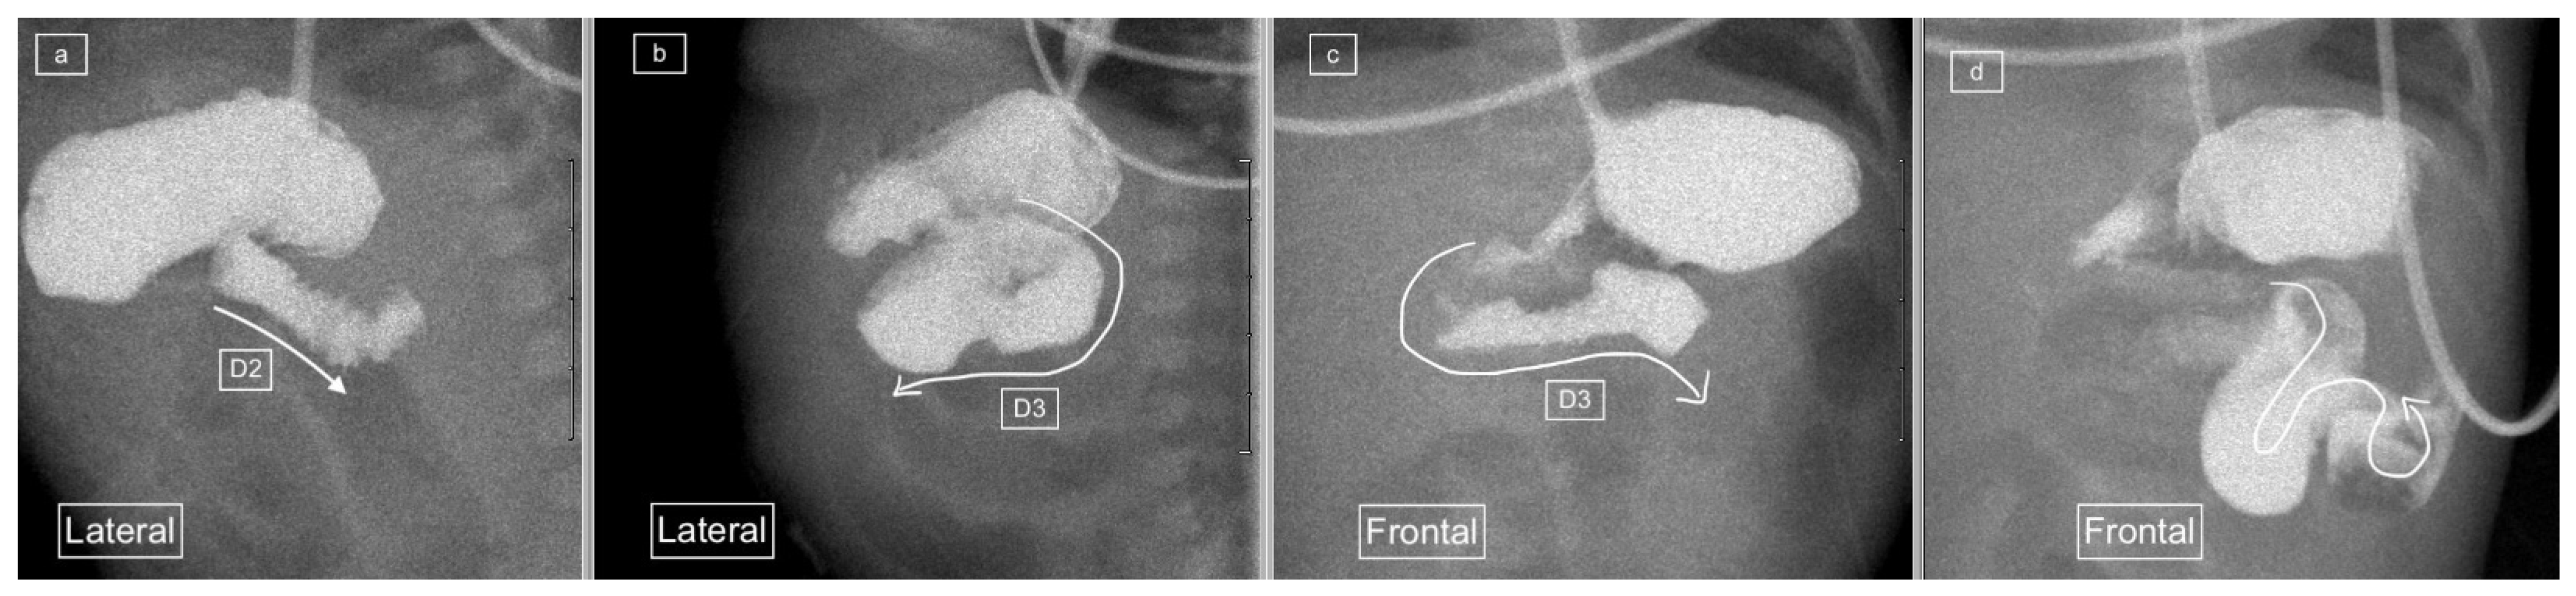

Figure 1.

(a) early and (b) later view: Sequential lateral views from an upper gastrointestinal tract study (UGIS) in an 8-year-old boy demonstrating the normal configuration of the duodenum which courses posteriorly (retroperitoneal) from the antrum (D1), descends posteriorly (D2), remains posterior at its most inferior portion (D3), ascends posteriorly again through (D4) and only then courses anteriorly from the duodeno-jejunal (DJ) flexure at the same height as the antrum and D1.